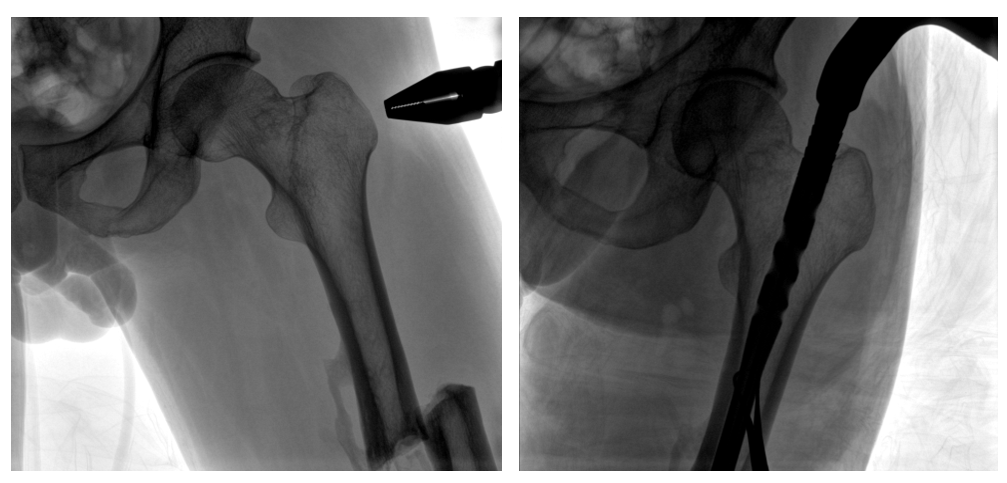

病例二:

患者左股骨干完全骨折,經(jīng)過(guò)醫(yī)生評(píng)估,使用“髓內(nèi)釘內(nèi)固定術(shù)”進(jìn)行治療。髓內(nèi)釘內(nèi)固定術(shù)需要將入釘點(diǎn)至骨折部位的影像完全展示,在一些長(zhǎng)骨的骨折中,對(duì)視野范圍要求高。

一體式C形臂釘點(diǎn)至骨折部位的臨床影像

在進(jìn)行髓內(nèi)釘內(nèi)固定術(shù)時(shí),醫(yī)生需要同時(shí)觀察到入釘點(diǎn)和骨折部位的情況,PLX119C大平板一體式C形臂能夠呈現(xiàn)更廣闊的成像面積,滿足大部分長(zhǎng)骨髓內(nèi)釘內(nèi)固定術(shù)的攝片需求。